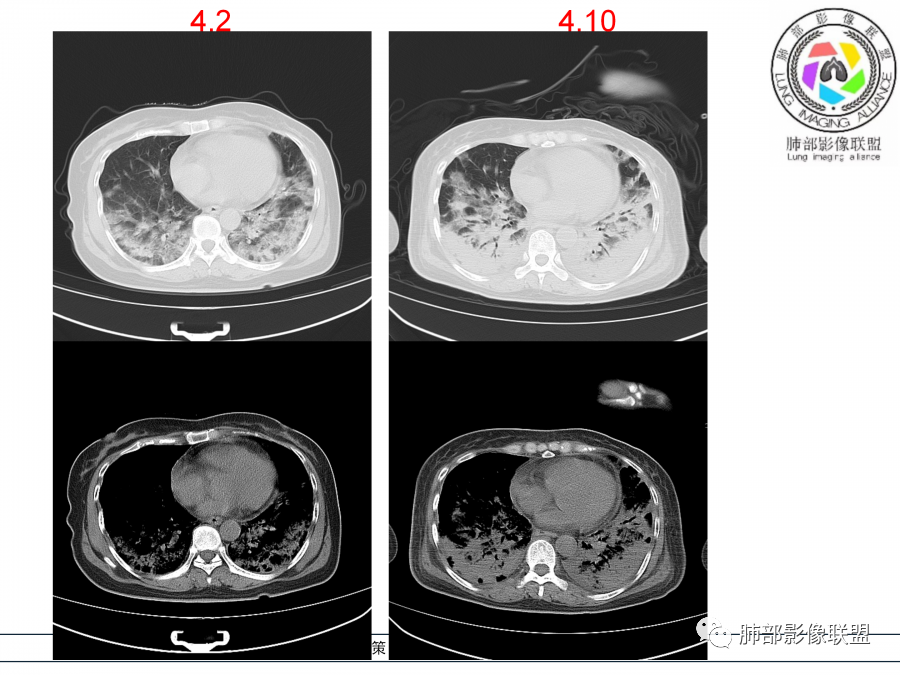

影像,第一次双肺中下叶胸膜下多发斑片状实变影,部分融合成,周围散发磨玻璃影,磨玻璃影内可见小叶间隔及小叶内间隔增厚,病变平行于胸膜,第二次间隔8天,双肺实变影明显进展,有重力作用,支气管近端堵塞,进展较快,临床有发热,血沉高,狼疮SLE阳性,考虑1:OP(机化性肺炎)2:SLE相关肺炎,建议支气管镜灌洗液病原学检测。

➢患者7天前起因受凉后出现阵发性咳嗽,无明显时间规律性,咳黄白粘痰,发热,体温最高达39.5℃,伴鼻塞、流清涕,。两肺下叶背段,后基底段为主的渗出性的病变,短时间内病变明显的增多,双侧胸腔积液,狼疮全套抗R0/SS检测阳性,考虑狼疮性肺损,机化性肺炎?鉴别结核

老年女性,高热,双肺下野近胸膜下片状高密度影,呈横向融合,双侧对称,抗炎治疗无效,复查病变进展明显,考虑狼疮SlE阳性结缔组织病相关的肺炎。

老年女性,咳嗽咳痰伴发热7天,白细胞不高,血沉快,降钙素原不高。其他化验未见明显异常,狼疮全套抗Ro/SSA阳性,双肺野靠近胸膜下磨玻璃实变影,支气管通畅,有充气征,沿胸膜下分布,有细网格征,7天后进展明显,实变影加重,胸膜肥厚,胸水不明显,心包少量积液?抗感染治疗无效,考虑非感染性疾病可能性大,结缔组织相关性肺病?狼疮性肺炎?机化性肺炎?鉴别病毒性肺炎。

老年女性,咳嗽咳痰发热7天。无气促。白细胞计数不高,PCT稍高,PPD(+),抗Ro/SSA阳性。CT:双肺野靠近胸膜下磨玻璃实变影,支气管通畅,有充气征,沿胸膜下分布,有细网格征。予抗生素治疗,8天后复查胸部CT见病灶范围扩大,实变影加重,胸膜肥厚,胸水不明显。抗感染治疗无效,考虑有:1.非感染性疾病:结缔组织相关性肺病,支持点:肺部CT表现为间质性炎症病变,抗RO/SSA(52)阳性;2.病毒性肺炎:患者无气促症状,可能性小;3.肺结核。

第一次双肺中下叶胸膜下多发斑片状磨玻璃及实变影,病变平行于胸膜,支气管通畅,8天后,双肺实变影明显进展范围扩大,部分支气管近端堵塞,进展较快,胸腔积液,抗感染治疗无效,考虑:非感染性疾病:结缔组织相关性肺病。鉴别机化性肺炎。

老年女性,咳嗽咳痰发热。PCT稍高,PPD(+),抗Ro/SSA阳性。CT:双下肺平行胸膜下实变影,支气管充气,有细网格征。一周抗炎复查病灶范围扩大,实变影加重,考虑结缔组织相关性肺病,sle_ss_ild?狼疮性肺炎?除外病毒性肺炎、肺结核。